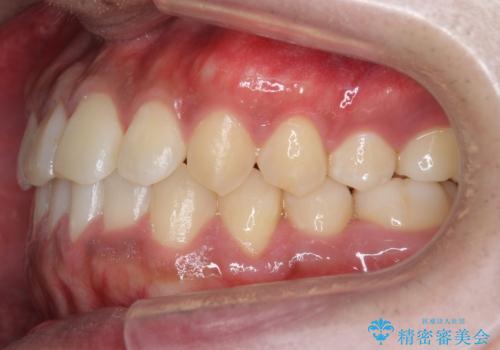

骨格性の受け口の矯正 部分ワイヤーで上の前歯を前に、 マウスピースで下の前歯を後ろに。

- 受け口を主訴に来院。

前歯のかみ合わせが逆になり上の前歯が奥に入っていました。